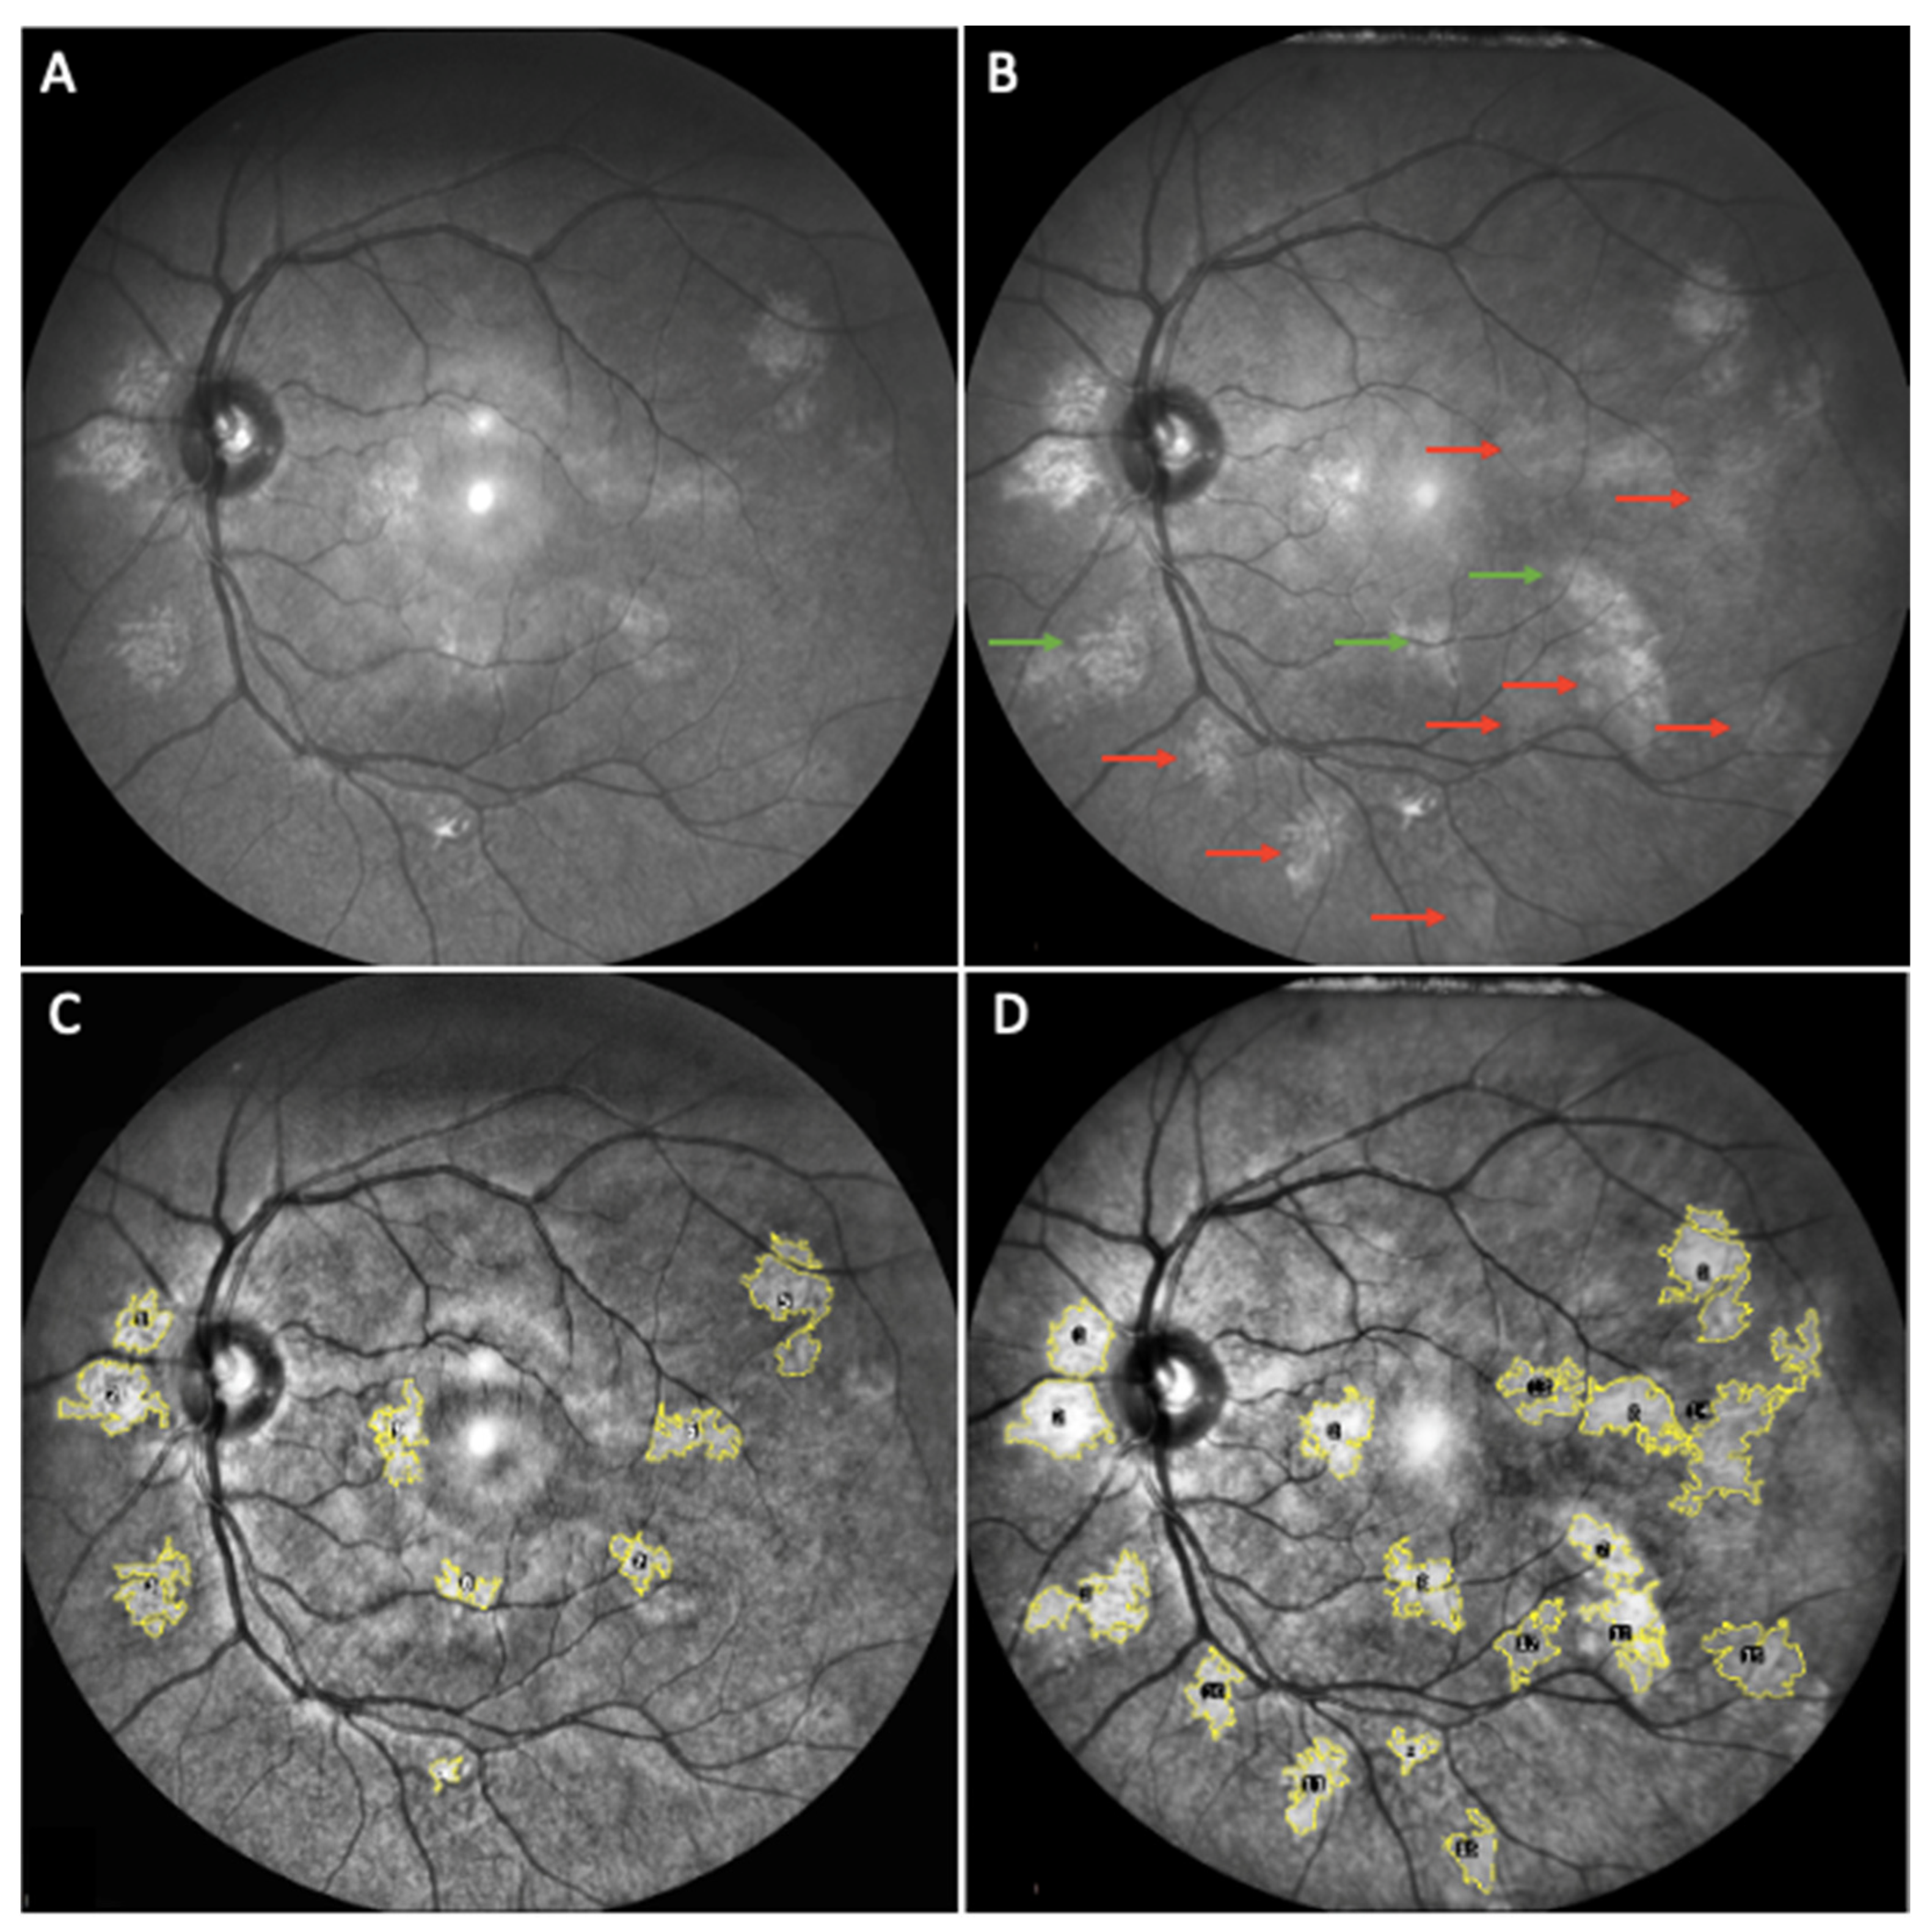

- Parrozzani, R.; Clementi, M.; Frizziero, L.; Miglionico, G.; Perrini, P.; Cavarzeran, F.; Kotsafti, O.; Comacchio, F.; Trevisson, E.; Convento, E.; et al. In vivo detection of Choroidal abnormalities related to NF1: Feasibility and comparison with standard NIH diagnostic criteria in pediatric patients. Investig. Ophthalmol. Vis. Sci. 2015, 56, 6036–6042. [Google Scholar] [CrossRef]

- Vagge, A.; Camicione, P.; Capris, C.; Sburlati, C.; Panarello, S.; Calevo, M.G.; Traverso, C.E.; Capris, P. Choroidal abnormalities in neurofibromatosis type 1 detected by near-infrared reflectance imaging in paediatric population. Acta Ophthalmol. 2015, 93, e667–e671. [Google Scholar] [CrossRef]

- Viola, F.; Villani, E.; Natacci, F.; Selicorni, A.; Melloni, G.; Vezzola, D.; Barteselli, G.; Mapelli, C.; Pirondini, C.; Ratiglia, R. Choroidal abnormalities detected by near-infrared reflectance imaging as a new diagnostic criterion for neurofibromatosis 1. Ophthalmology 2012, 119, 369–375. [Google Scholar] [CrossRef] [PubMed] [Green Version]

- Chilibeck, C.M.; Shah, S.; Russell, H.C.; Vincent, A.L. The presence and progression of choroidal neurofibromas in a predominantly pediatric population with neurofibromatosis type-1. Ophthalmic Genet. 2021, 42, 223–229. [Google Scholar] [CrossRef]

- Touzé, R.; Manassero, A.; Bremond-Gignac, D.; Robert, M.P. Long-term follow-up of choroidal abnormalities in children with neurofibromatosis type 1. Clin. Exp. Ophthalmol. 2021, 49, 516–519. [Google Scholar] [CrossRef] [PubMed]